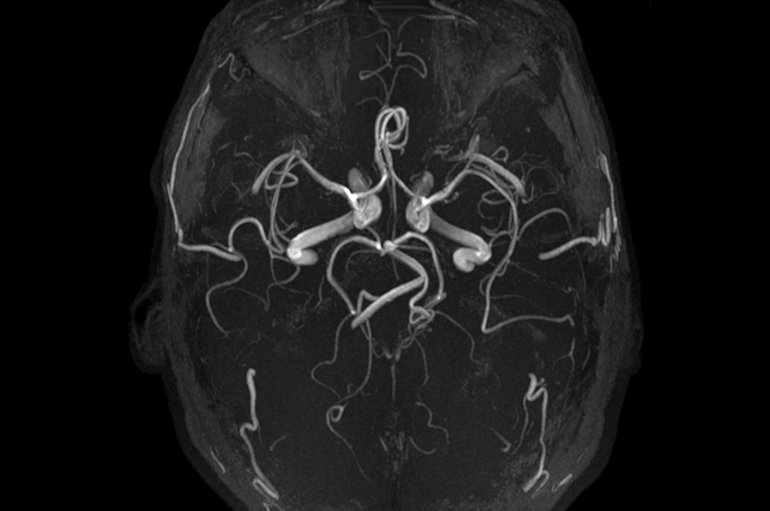

Существуют два основных метода ангиографии: КТ и МР. Первый метод, КТ, считается классическим и использует рентгеновские лучи. Второй метод, МР, применяет магнитное поле, аналогично магнитно-резонансной томографии. В зависимости от заболевания и сложности диагностики врач выбирает наиболее подходящий метод для исследования как крупных, так и мелких сосудов.

При проведении МР-ангиографии врач сначала делает серию снимков без контрастного вещества, а затем вводит препарат. После этого специалист повторно исследует сосуды, в которых уже накопилось контрастное вещество.

После анализа ангиограммы врач формирует соответствующие выводы. В норме костная ткань отображается белым цветом, а ликвор и здоровые сосуды — черным. При отсутствии патологий сосудистая система напоминает дерево с множеством крупных и мелких ветвей, а контрастное вещество равномерно распределяется по ней. Данное исследование помогает выявить различные отклонения, однако некоторые заболевания встречаются наиболее часто.